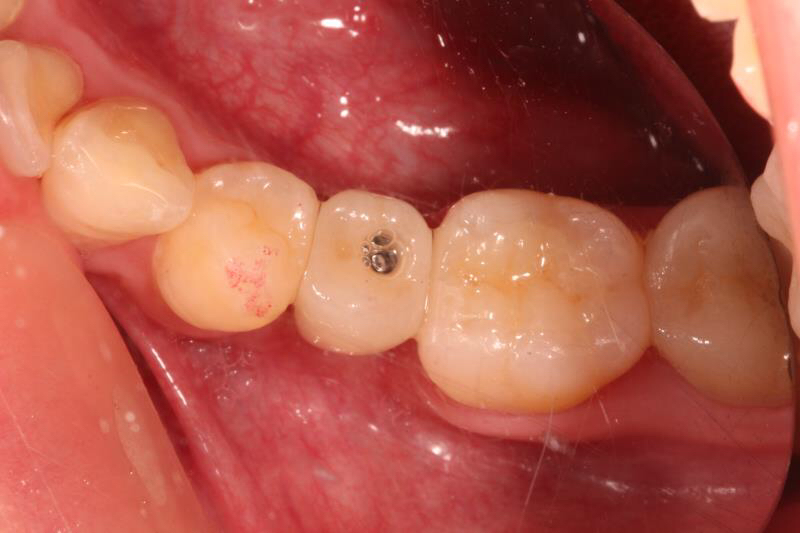

回到主题,老卢为这位小伙子采用即拔即种的方式,由于骨量条件尚可,植体植入后直接上愈合基台,这样就可以让患者提前了戴牙时间,早一些用上这颗牙齿吃东西。希望小伙子能体会老卢的良苦用心,以后好好保护自己的牙齿。